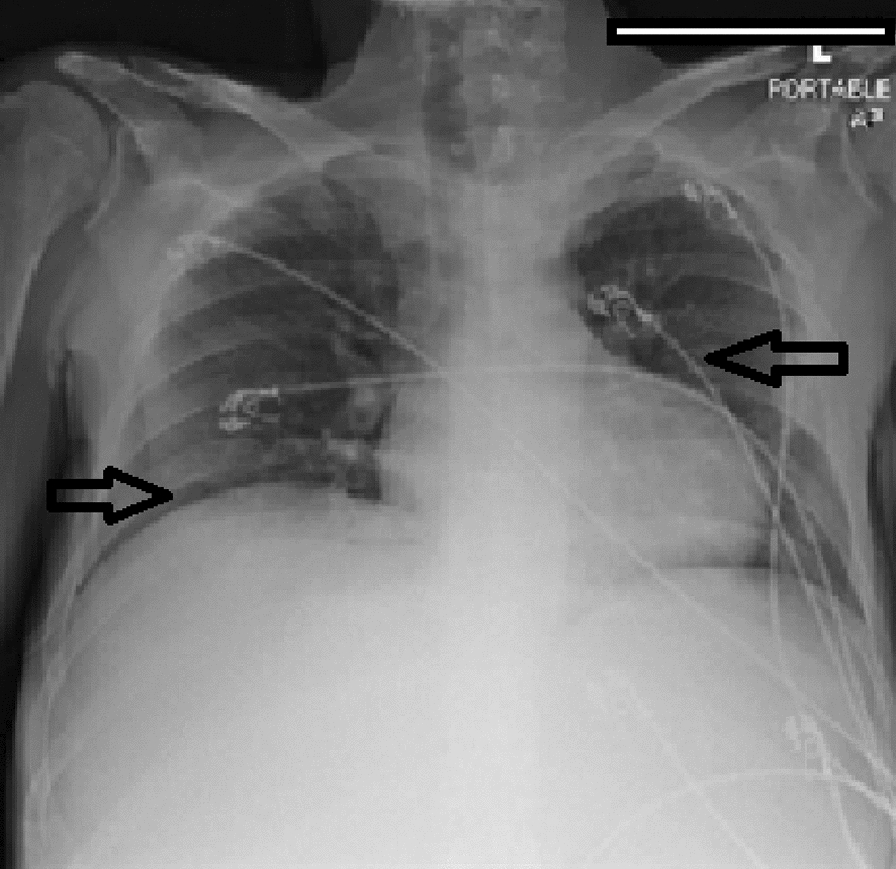

Hematology workup revealed mild leukocytosis (10.94 K/uL), normocytic anemia (hemoglobin 7.3 g/dL, mean corpuscular volume 94.4fL), and thrombocytosis (platelet count 901,000). Comprehensive metabolic panel was consistent with acute kidney injury (AKI) (creatinine 3 mg/dL, blood urea nitrogen 45 mg/dL—baseline unknown), tumor lysis syndrome (potassium 6.3 mmol/L, uric acid 21.7 mg/dL, phosphorus 5.6 mg/dL, and calcium 8 mg/dL). hyponatremia at 127 mmol/L, high anion gap metabolic acidosis (bicarbonate level 6, pH 7.23 on VBG, lactate 11.5), lactate dehydrogenase > 25,000 units/L, and elevated transaminases in a mixed pattern. Chest x-ray showed an ill-defined erosive mass of the left 4th to 5th lateral ribs, a thyroid mass, and trace pleural effusions (Fig. 1). Computerized tomography (CT) chest, abdomen, and pelvis had several significant findings pointing towards widespread malignancy. It showed a left supra-clavicular nodal mass measuring 5.4 × 4 × 3.6 cm, diffusely heterogeneous liver possibly reflecting metastatic disease, nodular soft tissue densities along with the hepatic capsule suspicious for hepatic capsular implants, large volume abdominopelvic ascites with extensive peritoneal soft tissue thickening/omental caking compatible with peritoneal carcinomatosis, mass-like thickening of the rectum, numerous lytic lesions involving the bilateral scapula, multiple ribs, bilateral proximal humerus, numerous vertebral bodies, pelvic bones, and proximal femur (Fig. 2). CT Head showed numerous diffuse lytic calvarial lesions concerning metastatic disease, but no mass effect was seen (Fig. 3).

Fig. 1.

Chest x-ray showing trace bilateral pleural effusions and ill-defined erosive mass of left fourth and fifth rib